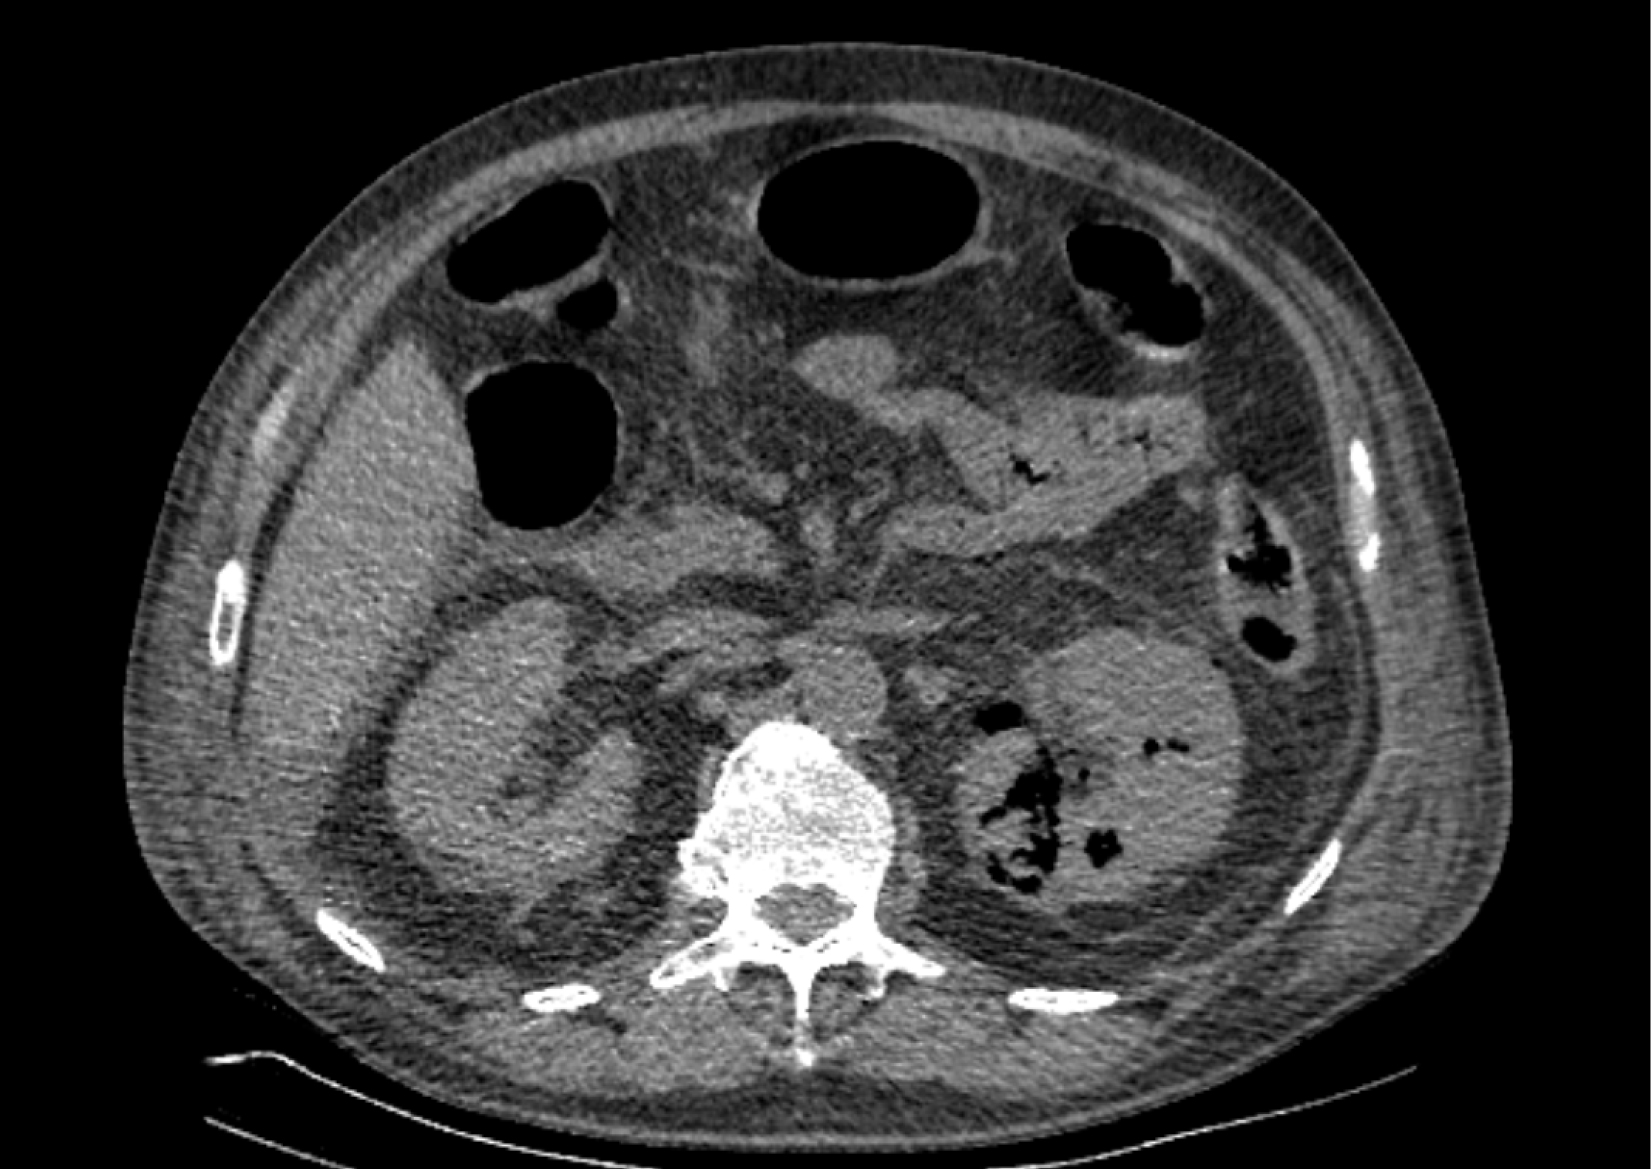

На следующий день состояние пациента оставалось тяжелым, с отрицательной динамикой, креатинин сыворотки возрос до 735,2 ммоль/л, Появились жалобы на слабость, тошноту. При осмотре: живот мягкий, вздут по всем отделам, при пальпации болезненный. Область почек не изменена, при пальпации безболезненна, патологических изменений в области почек не выявлено. Симптом поколачивания отрицательный билатерально. При УЗИ были обнаружены плевральный выпот по 300–400 мл с каждой стороны, гепатомегалия, увеличение размеров селезенки, асцит. Кроме того, в обеих почках были визуализированы тени, характерные для конкрементов. По данным компьютерной томографии (КТ) конкрементов не обнаружено, но в лоханке, на всем протяжении левого мочеточника и, частично, в правом мочеточнике, а также в мочевом пузыре визуализировался газ (рис. 1–6).

Рис. 1. Компьютерная томография органов брюшной полости, забрюшинного пространства, органов малого таза. Газ в мочевом пузыре

Рис. 2. Компьютерная томография органов брюшной полости, забрюшинного пространства, органов малого таза. Газ в мочевом пузыре

Рис. 4. Компьютерная томография органов брюшной полости, забрюшинного пространства, органов малого таза. Газ в почках